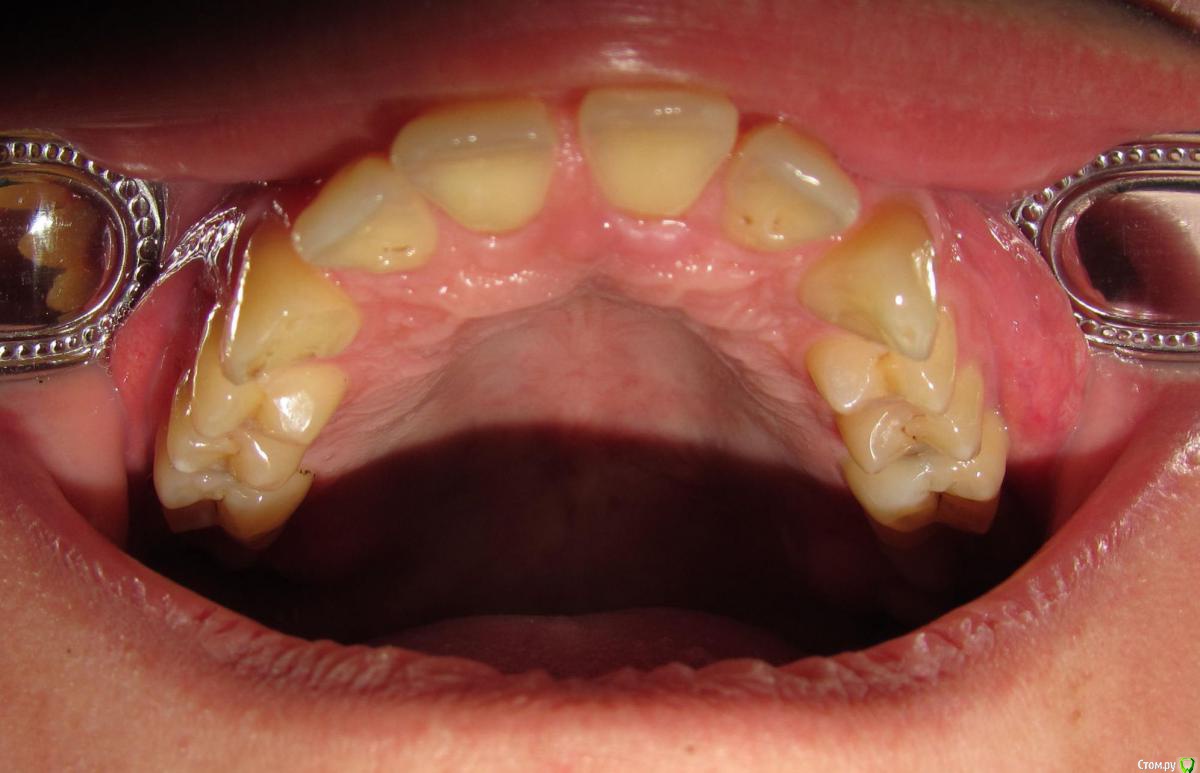

janis1 Опубликовано 14 ноября, 2015 Поделиться Опубликовано 14 ноября, 2015 Доброго времени суток, уважаемые профессионалы.Очень надеюсь на вашу помощь.Коротко о себе:37 лет, пол мужской. Так сложилось что в последнее время меня постигло сразу три проблемы,как мне кажется все они имеют между собой четкую связь. Основная проблема, с болями верхней челюсти, началась у меня около месяца назад. Боль не очень сильная, но практически постоянная. Боль не имеет какой-либо конкретной локации (болит именно вся челюсть). С утра она меньше, ближе к вечеру усиливается. В последнее время немного отдаёт в скулу. Одновременно с появлением боли, во рту, в районе дёсен, появился как бы привкус соды (немного похожий на вкус крови, но крови в ротовой полости нет).И в довершение всего начали катастрофически искривляются зубы верхней челюсти.На самом деле проблемы с прикусом у меня были уже с детства, примерно в 10 - 12 лет я носил пластинку для исправления прикуса.Но к сожалению лечение так и не закончил, соответственно прикус все это время у меня был неправильным, но до последнего времени он меня не беспокоил, так как был если так можно сказать "в пределах разумного", и в течении долгого времени был неизменен, но в последние несколько месяцев верхние зубы искривились настолько катастрофически что что я реально начал шепелявить. При попытке расшатывания зубы стоят крепко, не болтаются. Пока во всяком случае... Со всеми этими проблемами я пробовал обращаться к зубному хирургу и ортодонту,ни хирург, ни ортодонт к которым я обращался не смогли назвать каких-либо конкретных причин по которым может появляться боль в верхней челюсти и привкус во рту.Врачи к которям я обращался действительно хорошие специалисты, но похоже видят проблемы узко по своей специализации.Единственно хирург указал на то, что возможно придется удалять восьмерки, а ортодонт предложил установить брекеты на обе челюсти.Я прекрасно понимаю что с таким прикусом мне действительно не избежать установки брекетов, но меня беспокоит то, что не найдена причина происхождения всех проблем о которых я написал. Очень надеюсь на вашу помощь в поиске возможных причин проявления моих проблем. Заранее благодарен! Ссылка на комментарий

Jurai Опубликовано 22 ноября, 2015 Поделиться Опубликовано 22 ноября, 2015 Есть проблема во фронтальном участке верхней челюсти: общая убыль костной ткани, ячеистая структура кости. смещение зубов так, что корни изогнулись, это значит, что либо резорбция (рассасывание) либо очень длительное уже идет воздействие. Могу подозревать новооборазование в этом участке.Вам нужна консультация челюстно-лицевого хирурга-онколога. 1 Ссылка на комментарий

janis1 Опубликовано 29 ноября, 2015 Автор Поделиться Опубликовано 29 ноября, 2015 Рекомендую начать с малого Вы знаете, с "малого" я уже кажется начинал. С момента появления болей, я был 5 раз на приёме у 4 разных специалистов: 1. хирург 2. ортодонт. 3 гигиенист (делал гигиену) 4. эндодонт 5. снова ортодонтВ последний визит у ортодонта я был уже с данными КТ и рекомендациями специалистов с этого сайта. Правда вы в ваших рекомендациях упоминали вначале только 25 зуб. Так вот ортодонт (кстати действительно очень хороший специалист, о нём очень много положительных отзывов, и он действительно внимательно отнёсся к моим жалобам) после очного осмотра и просмотра КТ заключил, что зубы не могут являться причиной болей в моём случае...Как-то так...Хотя даже я - полный профан в этих вопросах, глядя на ваши скриншоты вижу, что там действительно есть какие-то "изменения"... Ссылка на комментарий

janis1 Опубликовано 14 декабря, 2015 Автор Поделиться Опубликовано 14 декабря, 2015 Итак, продолжение моей эпопеи.Удалось попасть к челюстно-лицевому хирургу-онкологу раньше чем было запланировано. После очного осмотра и изучения КТ, профессор выдал заключение, что никаких проблем по его части он не нашел.После этого я был у терапевта, по поводу 25 -26 зубов, ничего кроме зубного камня на 26 зубе (кстати напомню я недавно делал гигиену ) он так-же ничего не нашел.На всякий случай сделали рентген зубов, даже как я понял с двух сторон, вот снимки: Ну и самое главное - проблема осталась, то-есть уже более двух месяцев я живу с болью в районе верхней челюсти...Что делать дальше не знаю...Очень надеюсь на вашу помощь! Ссылка на комментарий